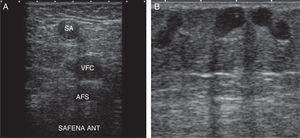

AnatomíaExisten dos fascias venosas, ambas hiperecogénicas y fácilmente identificables: la fascia muscular o profunda, que recubre planos musculares, y la superficial o venosa, que delimita el tejido celular subcutáneo11,12. Esto nos permite delimitar las redes venosas (fig. 1):

R2 o red secundaria: entre ambas fascias (signo del ojo) (fig. 2). Se localiza aquí el sistema venoso superficial compuesto por la vena safena interna (VSI), la vena safena externa (VSE), y sus variantes anatómicas (safena anterior y vena de Giacomini) (fig. 3A).

La VSI es el tronco más importante del sistema venoso superficial. Se origina en la cara anterior del maléolo interno y cruza desde la pierna hasta la ingle a través de la cara interna del muslo, para drenar a través de su cayado al SVP (vena femoral común, VFC).

La VSE se origina por detrás del maléolo externo y asciende por la línea media de la pantorrilla, drenando al SVP a nivel de la vena poplítea. En aproximadamente un tercio de los casos esta se continúa hasta la VSI a través de la vena de Giacomini, o bien drena al SVP a través de una perforante.